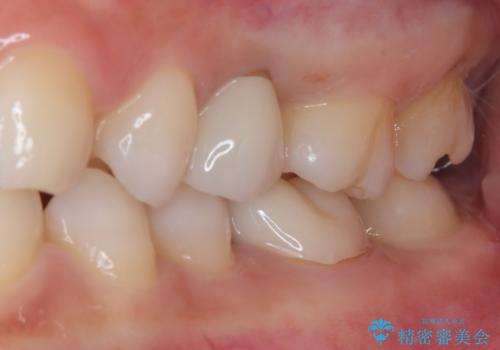

- 左上が虫歯になった気がするとのことで来院された患者様です。

左上の七番目と六番目の歯と歯が接するところに虫歯をレントゲン上で確認できました。

噛み合わせが強く、以前にも当院で右上でゴールドインレーにより治療をされていたのでゴールドインレーにて治療しました。

拡大鏡視野下で、虫歯の除去を行い、ゴールドインレーに適した形に整えました。